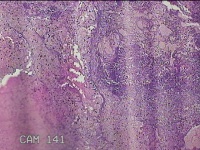

宫颈6点、10点、12点组织

性别

女

年龄

30岁

临床诊断

女性盆腔炎;宫颈炎性疾病;异常子宫出血

一般病史

宫颈HPV-56(+),TCT见非典型鳞状上皮细胞

标本名称

大体所见

1.“宫颈6点组织”:灰白暗红色不规则组织0.5x0.3x0.2cm一块。 2.“宫颈10点组织”:灰白暗红色不规则组织0.3x0.2x0.1cm一块。 3.“宫颈12点组织”:灰白暗红色不规则组织0.8x0.5x0.3cm两块。

图3

CIN1